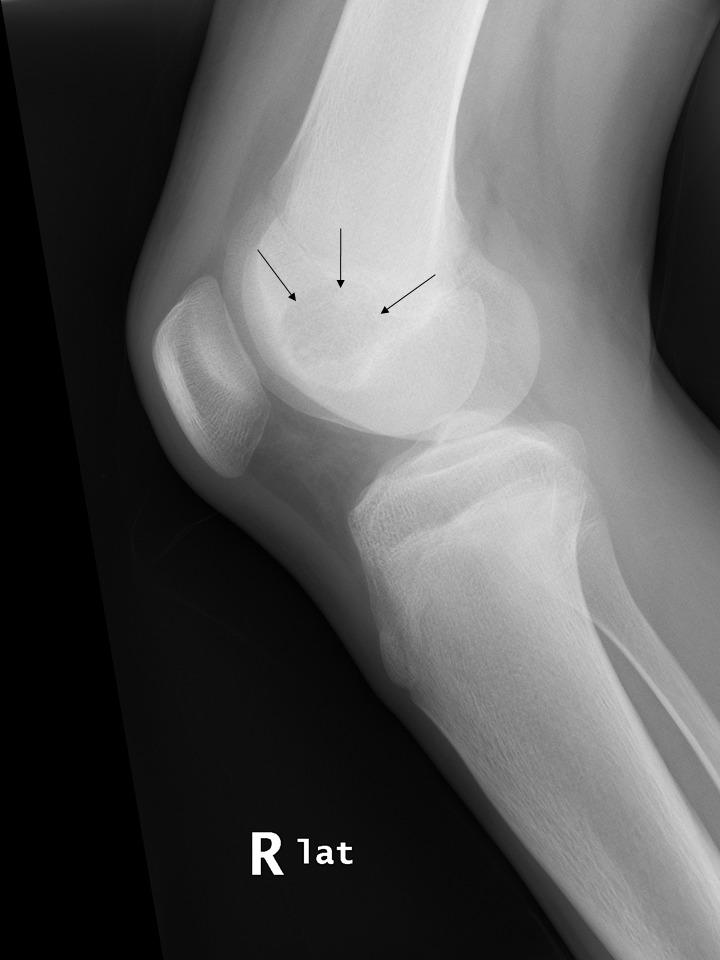

#PathQuiz 🔬🦴

A) Giant cell tumor of bone

B) Aneurysmal bone cyst

C) Chondromyxoid fibroma

D) Chondroblastoma

#Pathology #BonePath #OrthopedicPath

Clue in caption 🧐